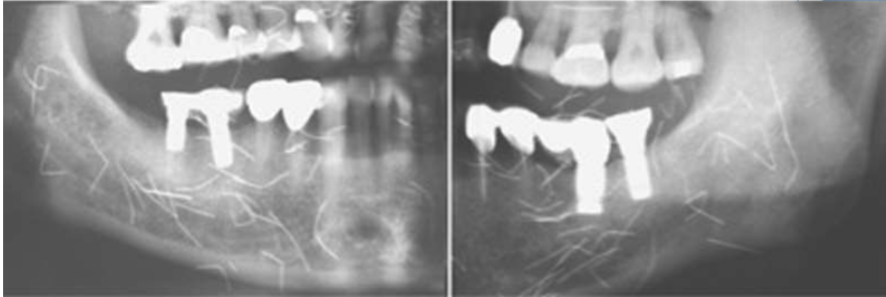

what is this

medication-related osteonecrosis of the jaws (MRONJ)